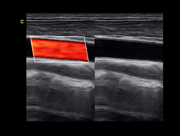

劲动脉 双实时模式